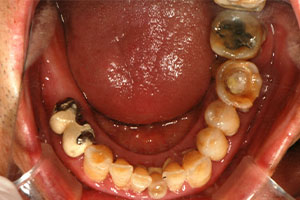

치료증례 전후사진

Before & After